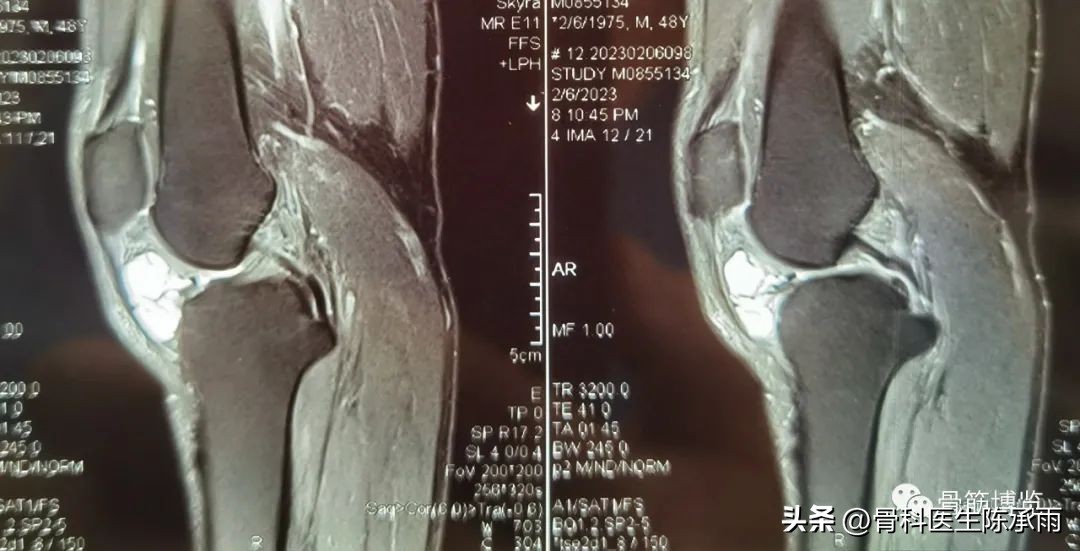

本例为内侧半月板前角巨大囊肿,关节镜下行半月板囊肿引流减压+囊肿前壁及囊壁滑膜切除+半月板缝合术。术中切除全部囊壁内滑膜及前壁及大部分后壁,保留部分后壁组织,以保证半月板前角缝合可靠及稳定。

术前影像